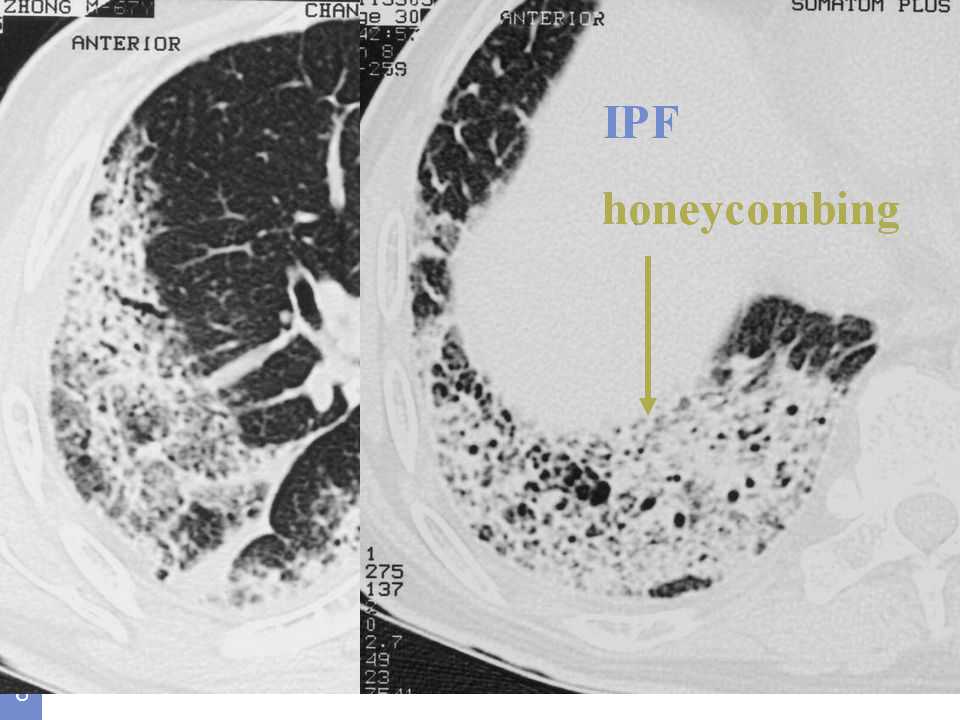

肺癌影像诊断